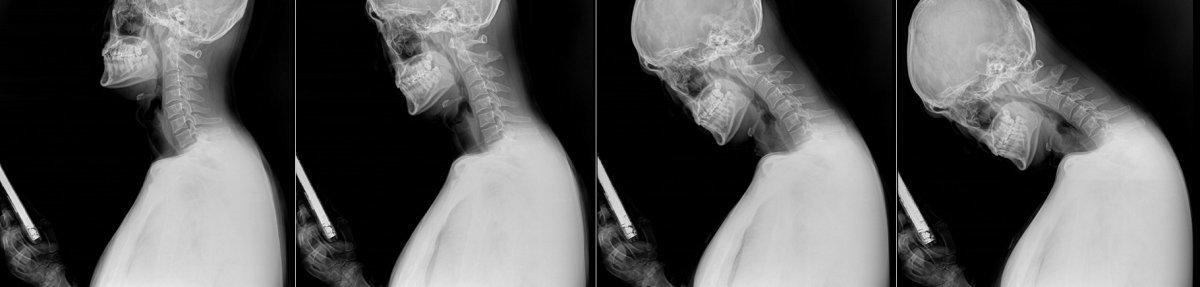

스마트폰을 이용할 때 목뼈와 척추의 모양을 찍은 X-레이. 이런 자세를 오래 하면 정상적이면 C자 모양을 해야할 목뾰가 일자목이나 거북목으로 변형되어 통증을 일으키게 된다 사진제공|바른세상병원

이근호 원장은 “장시간 구부정한 자세로 스마트폰이나 태플릿 등을 보는 바르지 못한 자세가 지속되면 정상일 때 C자로 있어야 할 목뼈(경추)가 일자목이나 거북목으로 변형되면서 통증을 일으키게 된다”며 “이렇게 정상적인 C커브를 잃은 상태가 장기간 지속되면 디스크가 튀어나와 신경을 압박하는 목 디스크로 발전할 수 있다”고 지적했다. 이어 “증상 초기에는 뻐근함이나 피로감 정도를 느끼지만 시간이 지날수록 어깨와 팔이 아프고, 심한 경우 손이나 팔 저림 증상으로 이어질 수 있다”고 주의를 당부했다.

고개를 숙이면 머리가 떨어지지 않도록 붙잡는 목 근육의 수축력이 함께 작용하면서 목에 가해지는 무게는 무려 머리 무게의 5배에 이른다. 성인 기준 머리 무게가 5kg이라면 목에 가해지는 무게는 25kg이나 되는 셈이다.